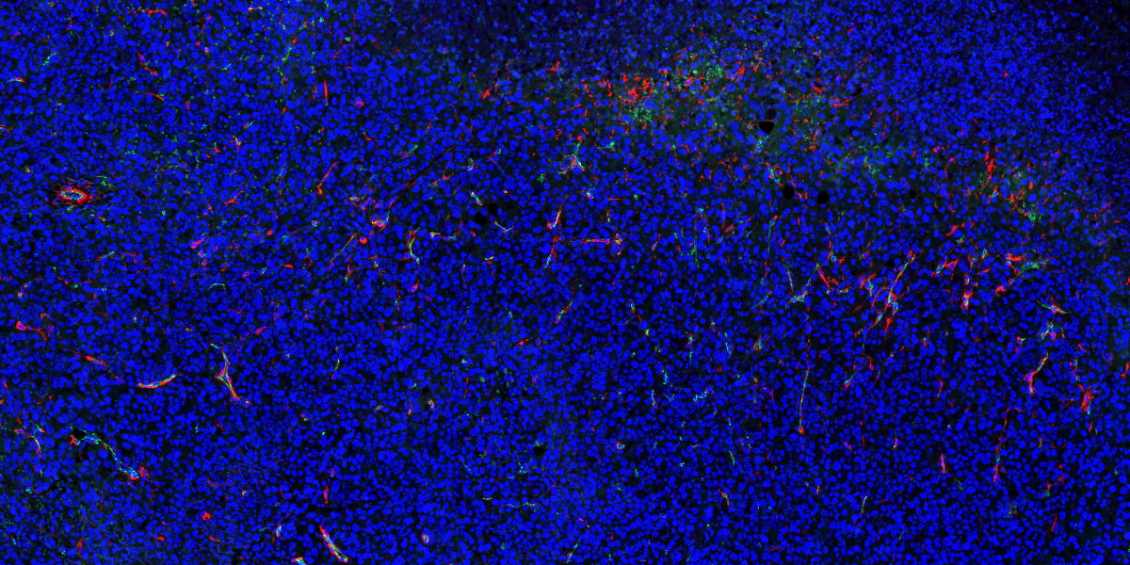

内蒙古石蜡切片免疫荧光不可避免会产生自发荧光。

1.取材的时候灌注取材,把红细胞冲洗干净;

2.脱蜡必须彻底,封闭、洗涤等过程也需充分;

3.抗体在使用前最好先离心处理并尽量从上方吸取,抗体的浓度过高也会产生自发荧光,所以可以预实验摸清最合适的抗体浓度再进行正式实验;

4.如若自发荧光很强,严重影响染色效果,亦可采用自发荧光去除剂进行去除。